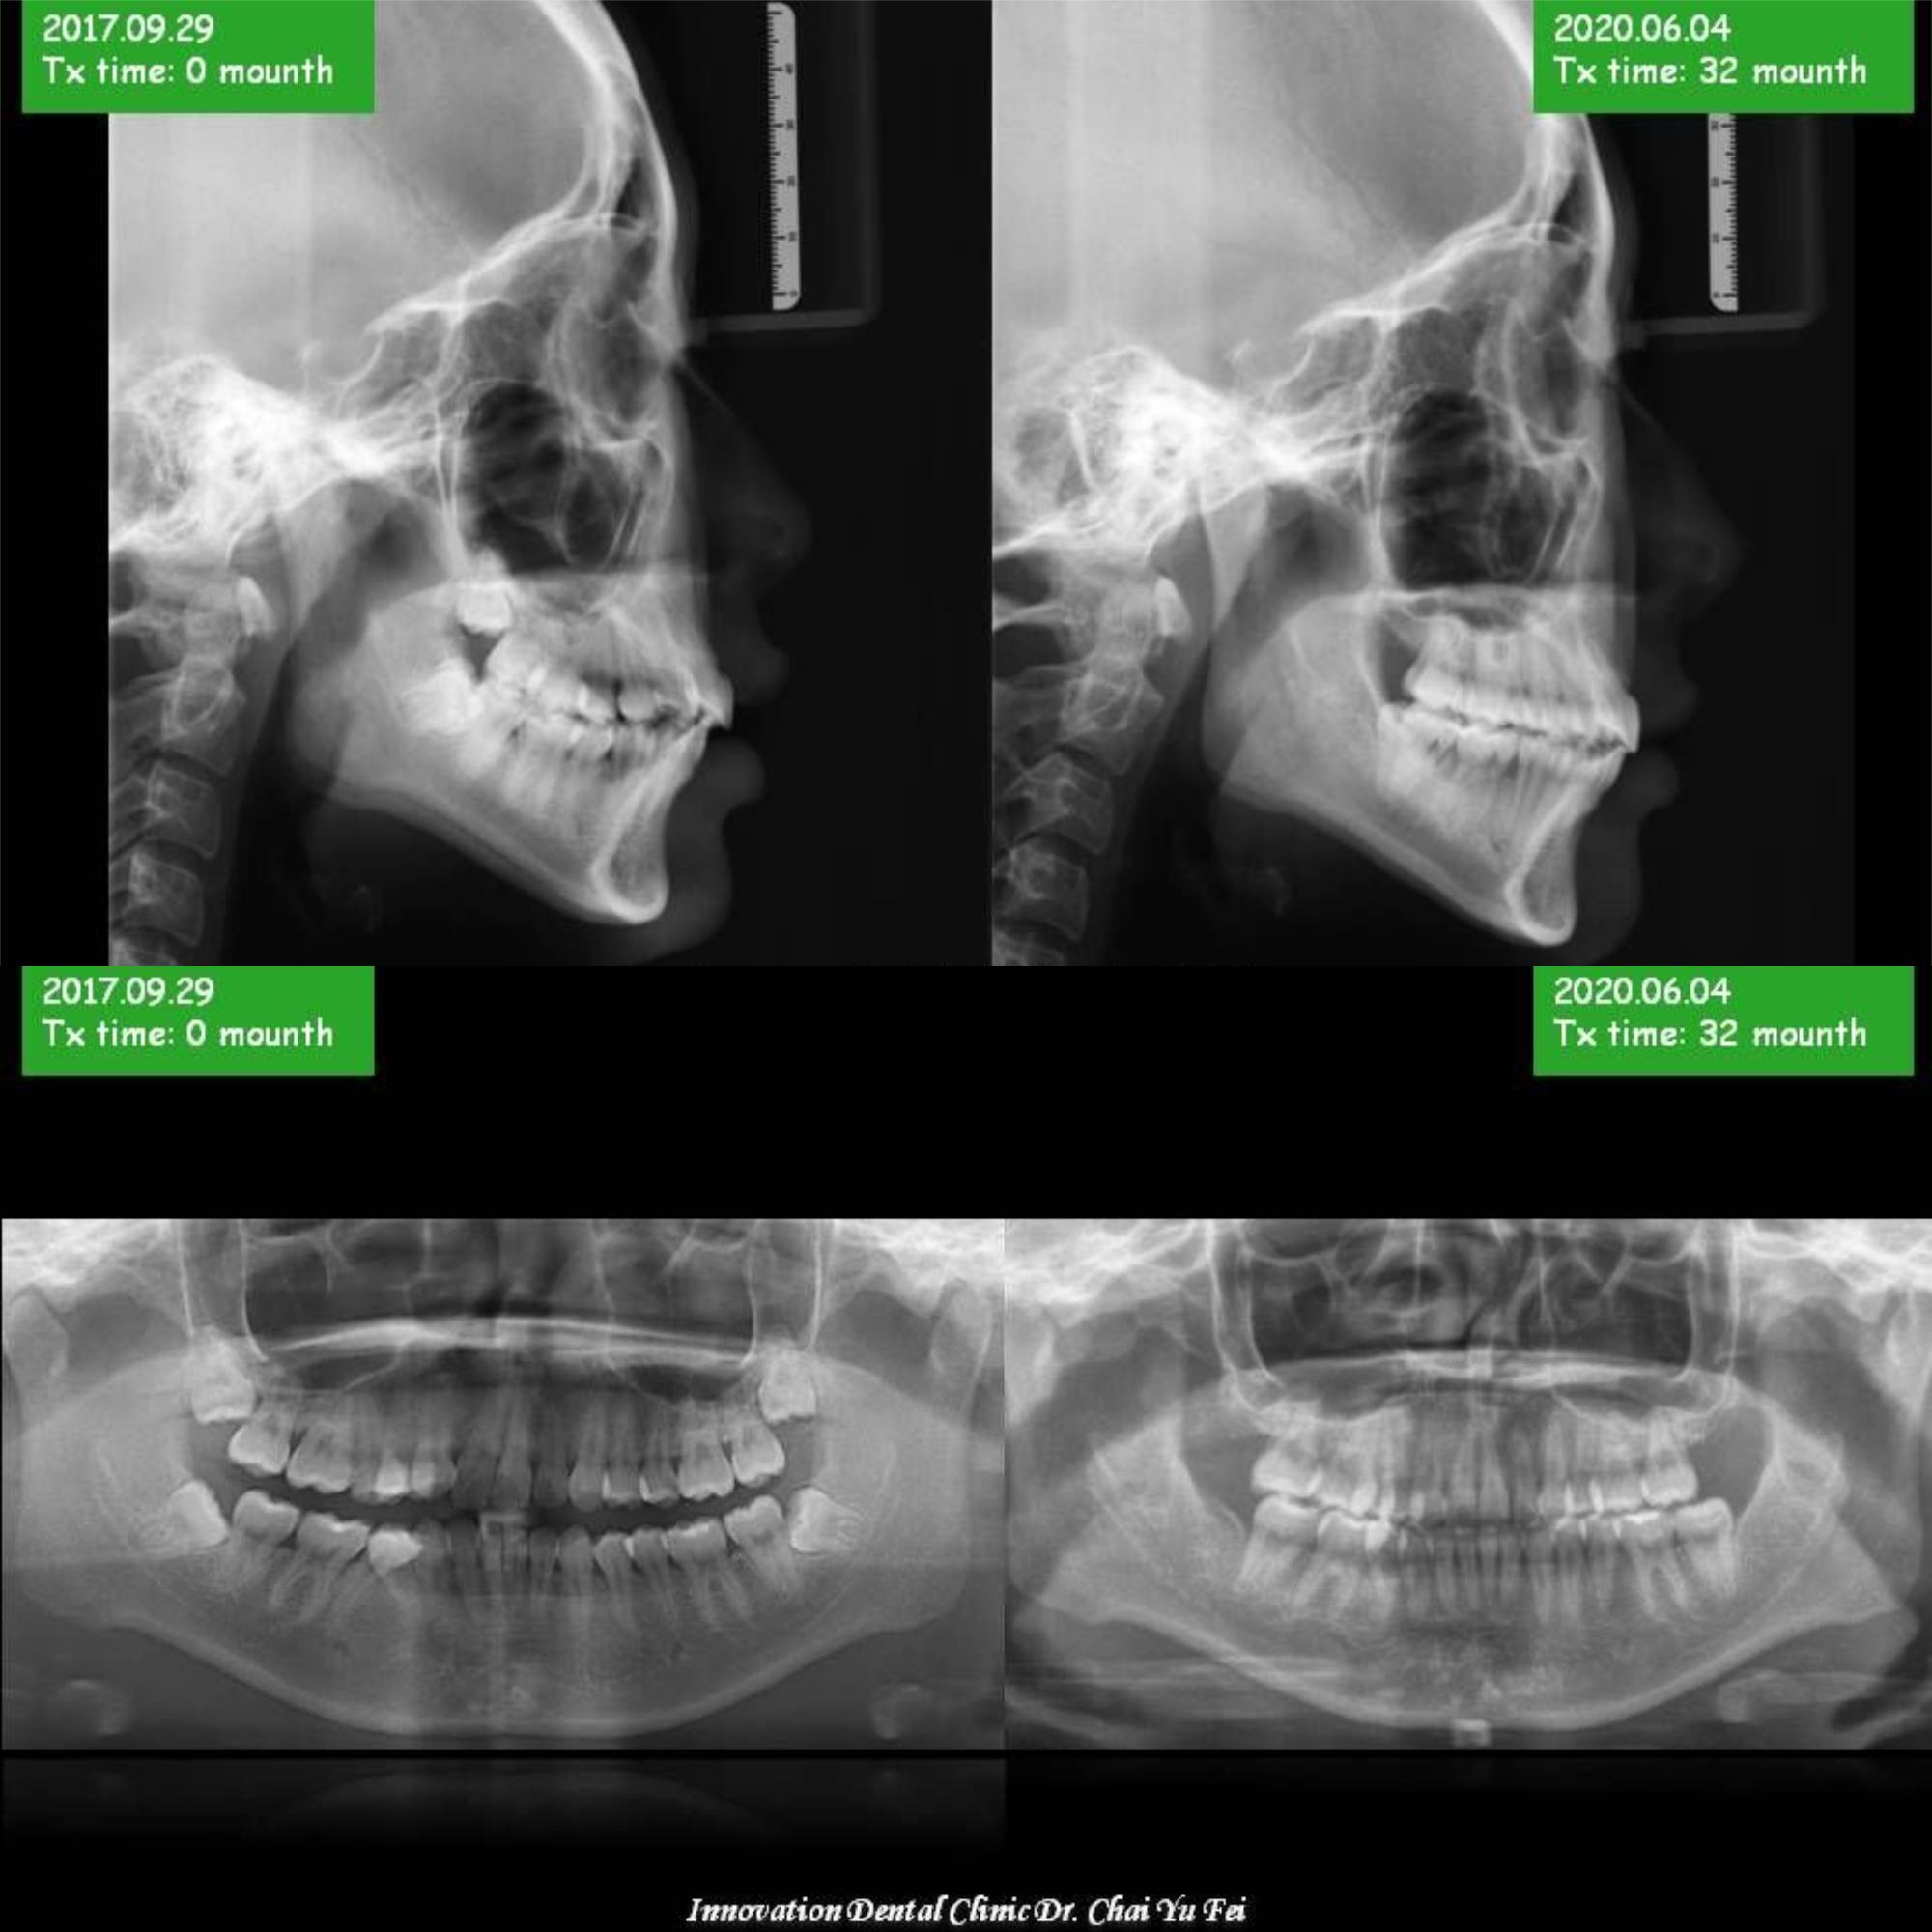

[ 矯正醫師 ] :  展心牙醫 翟聿飛 醫師

[ 治療方式 ] : 犬齒替代側門牙,小臼齒替代犬齒 不對稱拔牙矯正 ,利用拔牙空間將暴牙空間內收 ,改善原本嘴唇前突。

[ 治療時間 ] : 32 個月

上顎右側側門歯が先天性欠除による左右非対称,犬歯が側門歯に代わった、 小臼歯が犬歯に代わった.

上顎左側第一小臼歯、下顎右側第二小臼歯抜歯を行いました

上顎兩顆小臼齒的拔牙空間順利關閉。藉由骨釘後退達到理想咬合。下顎大臼齒立起來後,藉由下巴的移動改善唇型與輪廓。

▼ 治療前後の比較 (側方)

▼ 治療前後の比較 (上顎・下顎)